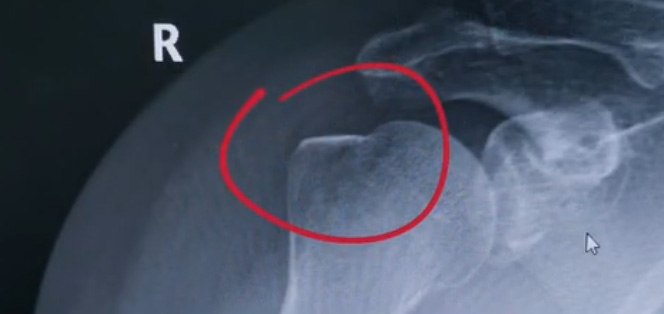

肩關(guān)節(jié)的X射線片子,看到?jīng)]有明顯的骨折,但是實(shí)際上已經(jīng)骨折了。那么是如何發(fā)現(xiàn)的呢?醫(yī)生對(duì)于做出疾病診斷的時(shí)候,會(huì)選擇什么樣的檢查方式。也更好的配合醫(yī)生,來解決問題。1米高的地方摔了下來,右側(cè)肩關(guān)節(jié)與地面相撞受傷了。當(dāng)時(shí)的胳膊還能活動(dòng),疼痛感很明顯,但是在家觀察了一天,這個(gè)腫脹沒有明顯的加重。然而問題是什么呢?疼痛始終不能緩解,所以就需要到醫(yī)院檢查。醫(yī)生查看關(guān)節(jié)的受限也很明顯,尤其做外展這個(gè)動(dòng)作的時(shí)候,幾乎沒辦法自行完成。肩關(guān)節(jié)內(nèi)的這個(gè)韌帶和肌腱可能還沒有發(fā)生嚴(yán)重的損傷。

首先做一個(gè)普通的X光檢查,看一看有沒有大的骨折或大的問題。結(jié)果是沒有發(fā)現(xiàn)太嚴(yán)重骨折損傷問題。結(jié)合病史,還是有點(diǎn)疑惑。因?yàn)樘鄣奶珔柡?。x光檢查和他的疼痛之間不匹配,患者沒有骨頭的損傷,疼痛不至于達(dá)到這么嚴(yán)重的一個(gè)程度。是否有一種情況掩蓋住了病情。這也是X線檢查的通病。x光檢查它是一個(gè)二維的檢查,有可能患者肩關(guān)節(jié)啊發(fā)生了骨折。但是它的位置被前方或者側(cè)方的這個(gè)骨頭遮擋住了。不是立體的就沒辦法看到后方的情況。想要更加進(jìn)一步的明確問題,判斷是否有骨頭的損害怎么辦?

進(jìn)一步就是查CT,可以更全面的角度去判斷問題的所在。就會(huì)發(fā)現(xiàn)是否骨折可以看到確實(shí)存在著骨折,還好骨折不算嚴(yán)重。可以說是一個(gè)骨裂。這個(gè)肩關(guān)節(jié)與地面撞擊的時(shí)候,暴力沒有達(dá)到那么強(qiáng)。讓骨頭整個(gè)發(fā)生一個(gè)巨大的斷裂,而是造成了一個(gè)小的劈裂。適當(dāng)?shù)倪M(jìn)行一些抗炎止痛藥的使用。適當(dāng)?shù)倪M(jìn)行一些消腫治療,患者癥狀也就消失了。